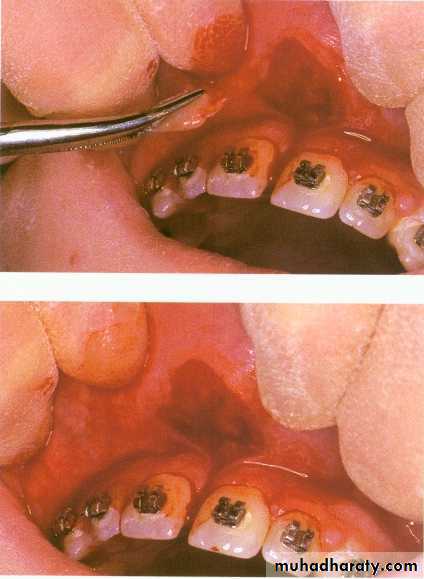

Under local anesthesia the upper lip is firmly retracted, demonstrating the extent of the fraenal attachment. If the frenum is particularly fibrous, its whole length is outlined and excised with a scalpel using an elliptical or rhomboid incision. The remaining fibres attached to the exposed bone can be curetted or gently removed with a bur but care must be taken not to damage the roots of adjacent teeth. The mucosa is then undermined and the defect closed with simple interrupted sutures. Patients are normally reviewed in 5–7 days.Lingual frenectomy